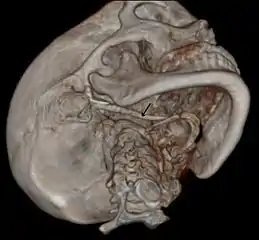

Imaging is important and is diagnostic. Visualizing the styloid process on a CT scan with 3D reconstruction is the suggested imaging technique.[12] The enlarged styloid may be visible on an orthopantogram or a lateral soft tissue X ray of the neck.